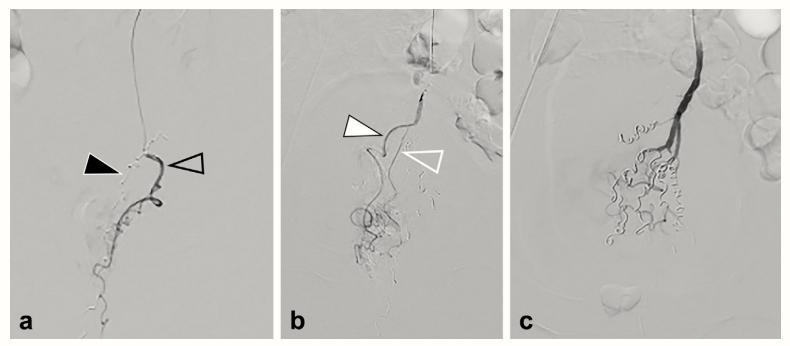

图3直肠上动脉血管造影术。

- 对直肠上动脉左后支(开放的黑色箭头)进行超选择性血管造影。

- 超选择性直肠上动脉造影显示直肠前支(白色箭头)和后支(开放的白色箭头)。(C)完全性直肠上动脉血管造影显示所有分支均有弹簧圈栓塞。